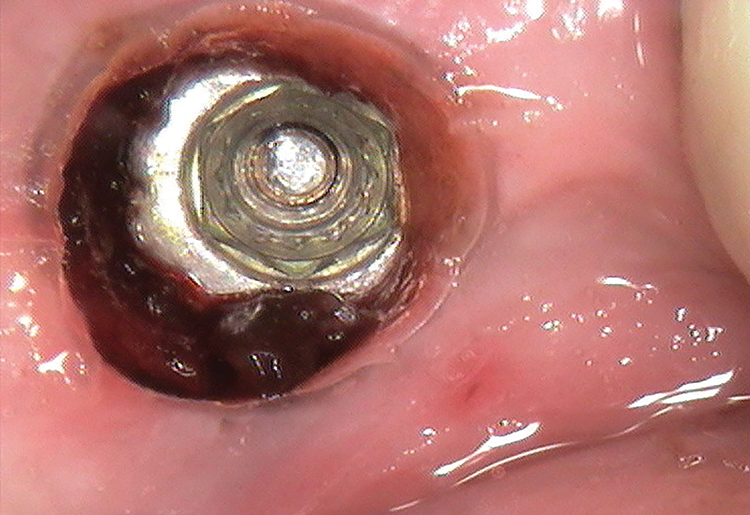

A 61-year-old male patient presented with the chief complaint of a missing implant-supported crown. The patient's dental history revealed a habit of grinding and clenching, and signs of wear were clinically evident during the examination. Because the implant restoration was placed 7 years prior at another practice, and the manufacturer and model were not immediately available, a universal protocol would be required to attempt the rescue. The patient reported that the crown had been dislodged for many weeks. As a result, the soft tissue had grown over the implant, completely covering it (Figure 2). A preoperative periapical radiograph was taken to help visualize the location and size of the remaining fragment (Figure 3). In addition, an intraoral camera would be used during the procedure to view the internal aspect of the fixture and aid in the retrieval process.

Once anesthesia was achieved, a periodontal probe was used to identify the extent of the implant platform, and then an appropriately sized biopsy punch was used to access the implant (Figure 4). Following access, a presoak of tartar and stain remover was injected into the fixture for a period of 10 minutes. This helped to remove any debris and corrosive elements that may have contributed to the difficulty of retrieval (Figure 5). A 0.36-mm capillary suction tip was used to remove the solution, and a new volume was deposited to penetrate the fixture as needed.